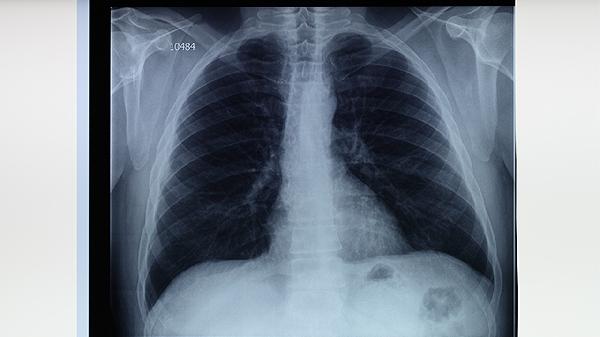

肺結(jié)核主要由結(jié)核分枝桿菌感染引起,傳播途徑包括飛沫傳播、密切接觸傳播、免疫力低下等因素。常見(jiàn)誘因有長(zhǎng)期熬夜、營(yíng)養(yǎng)不良、合并糖尿病或艾滋病等基礎(chǔ)疾病、居住環(huán)境擁擠通風(fēng)不良、未接種卡介苗等。肺結(jié)核屬于乙類(lèi)傳染病,需及時(shí)就醫(yī)隔離治療。

肺結(jié)核患者咳嗽、打噴嚏或說(shuō)話時(shí),會(huì)將含有結(jié)核分枝桿菌的飛沫排到空氣中。健康人吸入這些飛沫后可能被感染。在密閉擁擠的環(huán)境中,如監(jiān)獄、宿舍、醫(yī)院等場(chǎng)所傳播風(fēng)險(xiǎn)更高。預(yù)防措施包括佩戴口罩、保持室內(nèi)通風(fēng)、避免與患者密切接觸。

艾滋病患者、糖尿病患者、長(zhǎng)期使用免疫抑制劑者、營(yíng)養(yǎng)不良人群等免疫力低下者更易感染結(jié)核菌。結(jié)核菌可在體內(nèi)長(zhǎng)期潛伏,當(dāng)免疫力下降時(shí)發(fā)病。建議高危人群定期進(jìn)行結(jié)核菌素試驗(yàn)篩查,保證充足營(yíng)養(yǎng)和適度運(yùn)動(dòng)增強(qiáng)免疫力。

居住空間狹小、通風(fēng)不良的環(huán)境有利于結(jié)核菌傳播。人均居住面積小于4平方米、缺乏日照的潮濕環(huán)境會(huì)顯著增加感染風(fēng)險(xiǎn)。改善措施包括增加開(kāi)窗通風(fēng)時(shí)間、使用空氣凈化設(shè)備、控制居住密度,紫外線照射可有效殺滅空氣中的結(jié)核菌。

卡介苗接種可顯著降低兒童重癥結(jié)核病發(fā)生率。未接種者感染后易發(fā)展為粟粒性肺結(jié)核或結(jié)核性腦膜炎等嚴(yán)重類(lèi)型。我國(guó)新生兒需在出生24小時(shí)內(nèi)完成卡介苗接種,接種后2-3個(gè)月會(huì)形成疤痕,保護(hù)期可達(dá)10-15年。

糖尿病患者血糖控制不佳時(shí),肺泡巨噬細(xì)胞功能受損,結(jié)核病發(fā)病率是普通人群的3倍。塵肺病患者肺部清除功能下降,HIV感染者CD4細(xì)胞減少,均易繼發(fā)肺結(jié)核。這類(lèi)患者出現(xiàn)咳嗽咳痰超過(guò)2周時(shí)應(yīng)及時(shí)進(jìn)行痰涂片檢查。

預(yù)防肺結(jié)核需保持規(guī)律作息和均衡飲食,每日攝入足量?jī)?yōu)質(zhì)蛋白和維生素。建議高危職業(yè)人群定期體檢,出現(xiàn)持續(xù)低熱、夜間盜汗、消瘦等癥狀時(shí)及時(shí)就診。確診患者應(yīng)嚴(yán)格遵醫(yī)囑完成6-8個(gè)月規(guī)范治療,避免產(chǎn)生耐藥性。家庭成員需分室居住并做好物品消毒,密切接觸者應(yīng)接受預(yù)防性篩查。